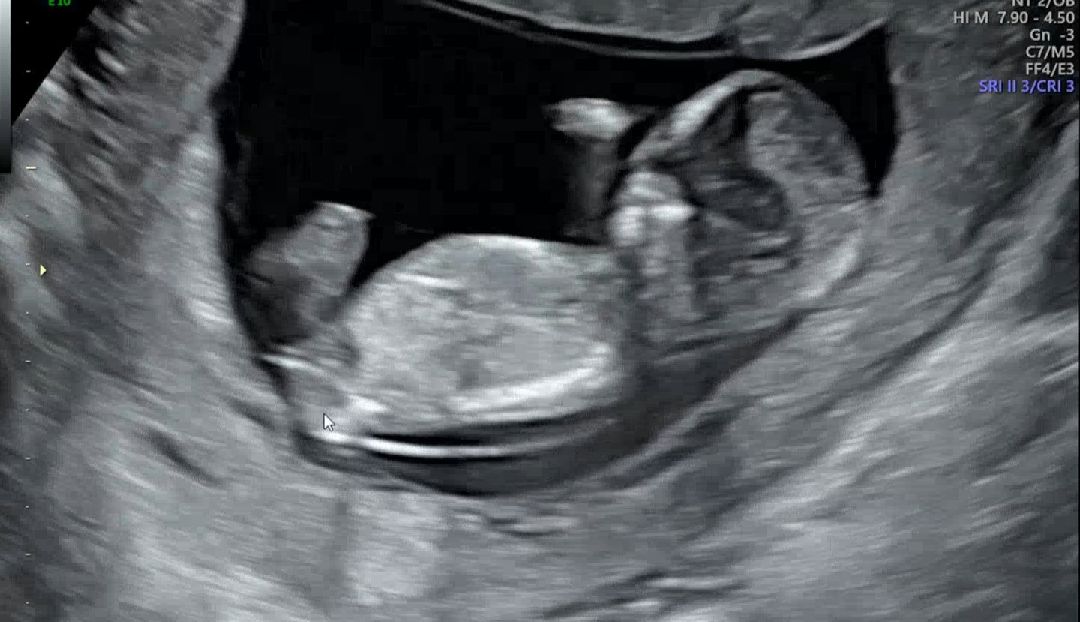

12주차 초음파 보고왔어요 ㅎ

제가 보기엔 성기결절이 평행에 가까워 보이는데 딸일까요 ㅎㅎㅎ